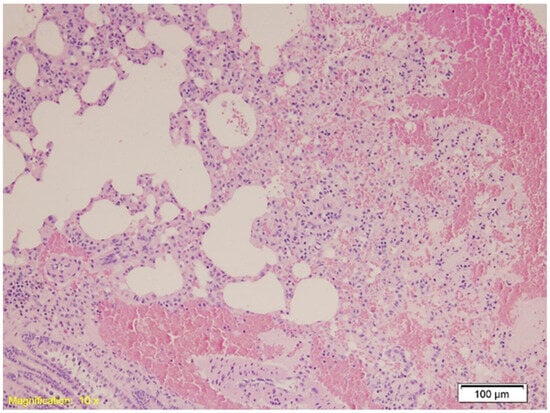

| Lungs | Congestion, emphysema, focal atelectasis, and intraalveolar and intraseptal hemorrhage, with emphysema most pronounced. | Slightly increased congestion, intraalveolar and intraseptal hemorrhage; emphysema less pronounced. | Similar to Group A with pronounced congestion, intraalveolar and intraseptal hemorrhage; less emphysema. |